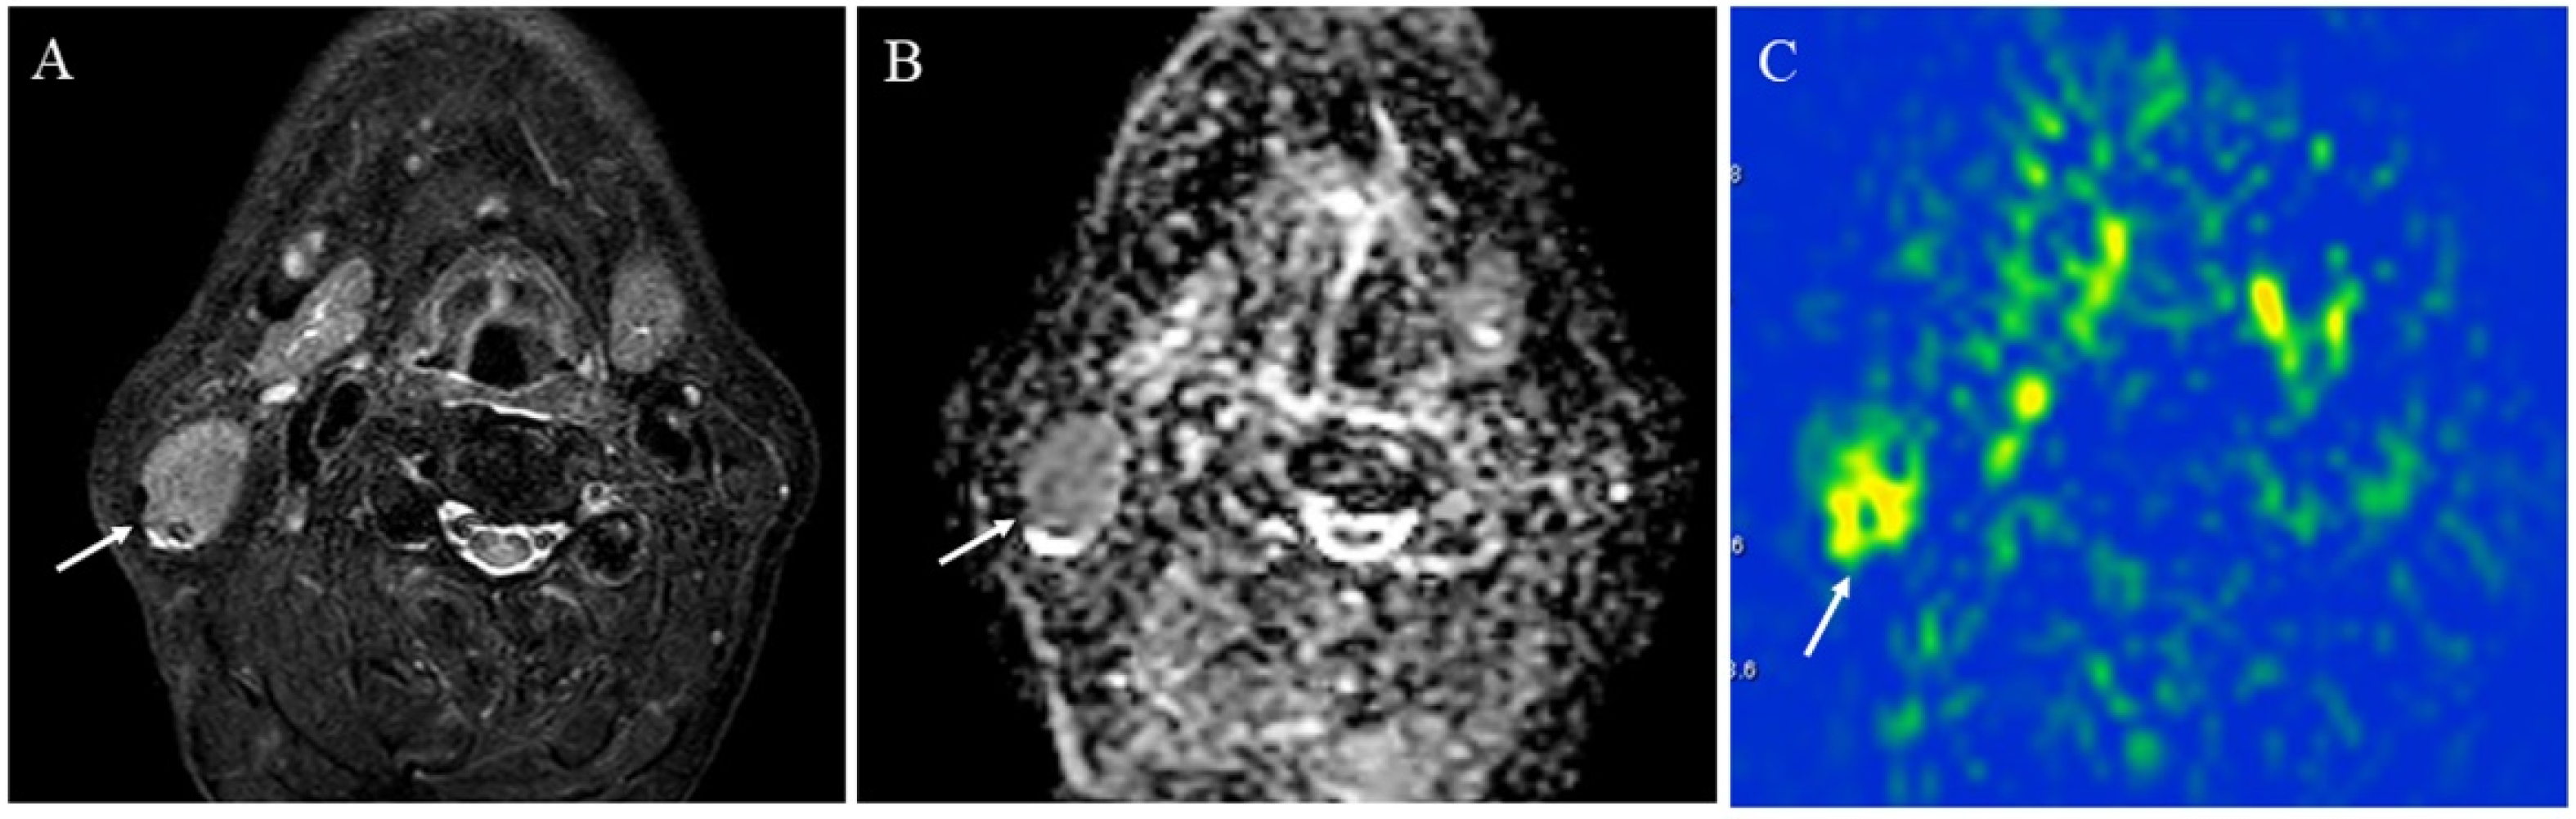

Figure 10. A 41-year-old female with pleomorphic adenoma of the left parotid gland: (A) STIR shows a mass with bright signal intensity (arrow); (B) ADC map shows increased diffusion (arrow) (ADC 10th percentile, 1.32 × 10−3 mm2/s and ADC mean of 1.48 × 10−3 mm2/s); (C) pCASL image shows low TBF (arrow) (TBF 50th percentile, 9.75 mL/100 g/min).